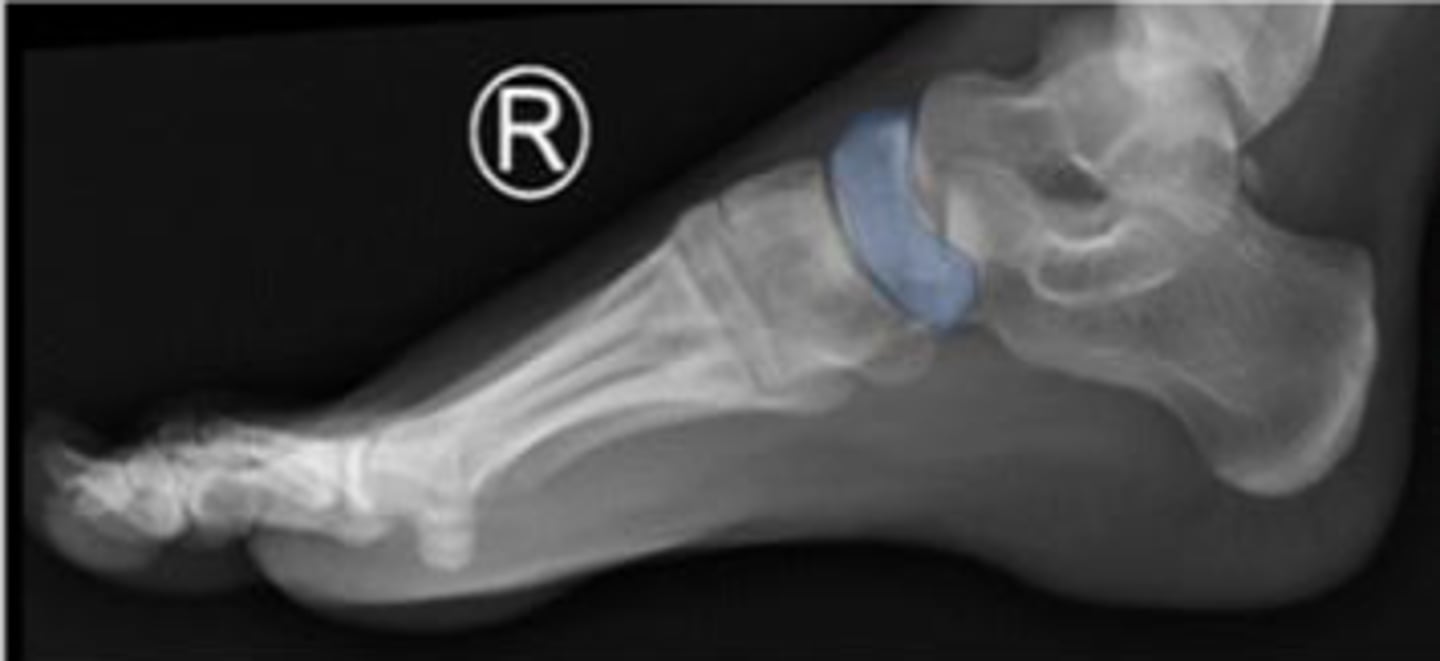

Right lateral foot

What is the name of the radiographic view?

Head of the talus of the right foot

What are the arrows pointing to?

Calcaneus of the right foot